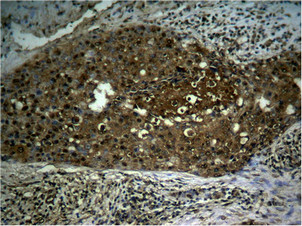

Immunohistochemical analysis of paraffin- embedded human breast carcinoma tissue using NFκB-p65 (Phospho-Ser276) antibody.

Immunohistochemical analysis of paraffin- embedded human lung carcinoma tissue using NFκB-p65 (Phospho-Ser276) antibody.